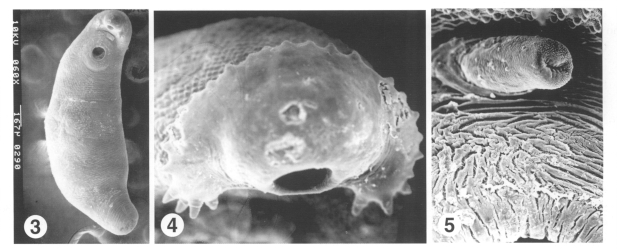

The flukes were processed for parasitological identification by light and scanning electron microscopic studies. The anterior of the fluke was bent ventrally at the acetabulum, and the surface was wrinkled transversely over the whole body. The body surface was covered with cobblestone-like cytoplasmic processes. Tegumental spines, scale-shaped with a broad base, were densely packed on the anterior surface of the body and then reduced in density and size on moving posteriorly (

Fig. 3). The anterior end bulged into a head crown around the oral sucker. The head crown was armed with uninterrupted 27 collar spines, of which the 4 end-group spines were present at the both ends of the the head crown (

Fig. 4). The outer surface of oral sucker was smooth and encircled with ciliated sensory (Type I) papillae arranged in 2-3 rows. Unciliated sensory (Type II) papillae, dome-like round structures, appeared on posterior half of the oral sucker lip. The acetabulum, wide-open, was aspinous with velvety cytoplasmic processes, and surrounded with Type I papillae. The cirrus erected from the genital opening revealed a velvety tegumental surface, and dense Type I sensory papillae, as compared with other parts of the body surface (

Fig. 5).

Fig. 3-5Scanning electron micrographs of an Echinostoma hortense specimen retrieved from the patient. Fig. 3. Ventral view. Fig. 4. The oral opening and head crown spikes with collar spines. Fig. 5. The cirrus erected from the genital pore anterior to the acetabulum.